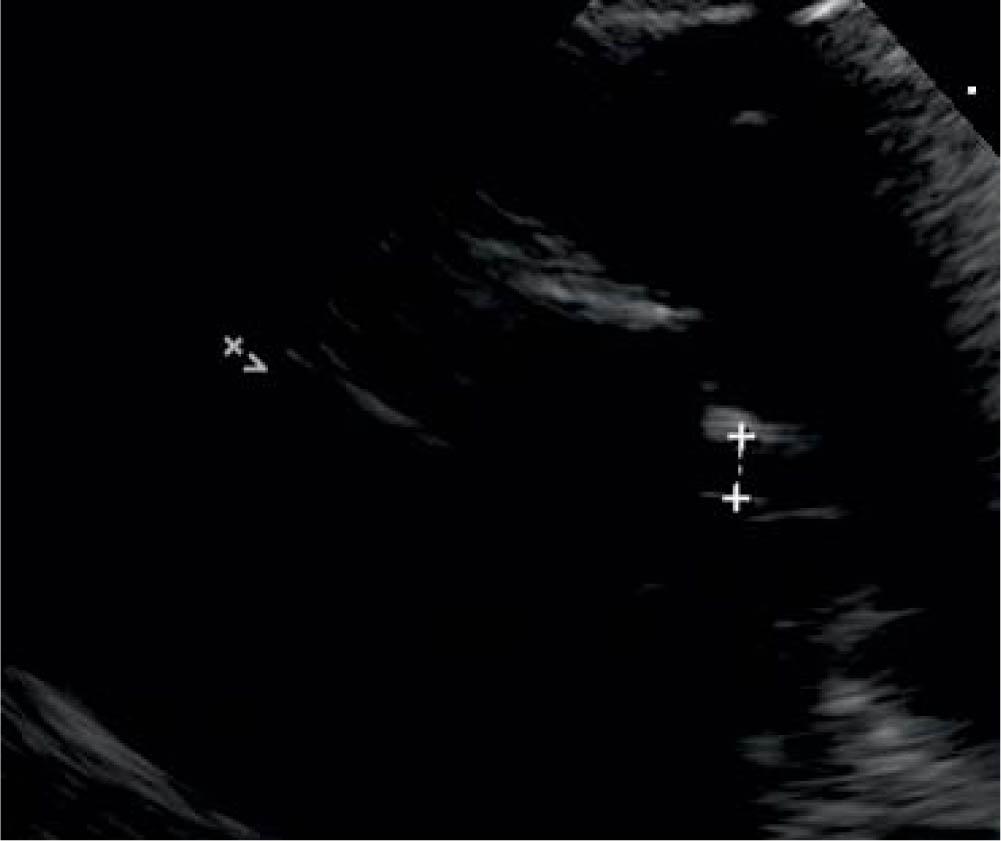

The electrocardiogram was normal. Repeated transthoracic echocardiography confirmed the moderate-severe systolic dysfunction (LVEF = 30–40%), the thin layer of pericardial effusion, a right pleural effusion of about 16 mm, Figure 1, mild mitral regurgitation, Figure 2, initial normal coronary artery diameter, but in evolution, in the fifth day dilated coronary arteries were noticed - the left main coronary artery measured 3.4 mm (Z-score = 2.8), the left anterior descending coronary artery measured 2.5 mm (Z-score = 2.6), and the right coronary artery was of normal size 2 mm (Z-score = 0.6) (Figure 3).

Figure 2

Mild mitral regurgitation.